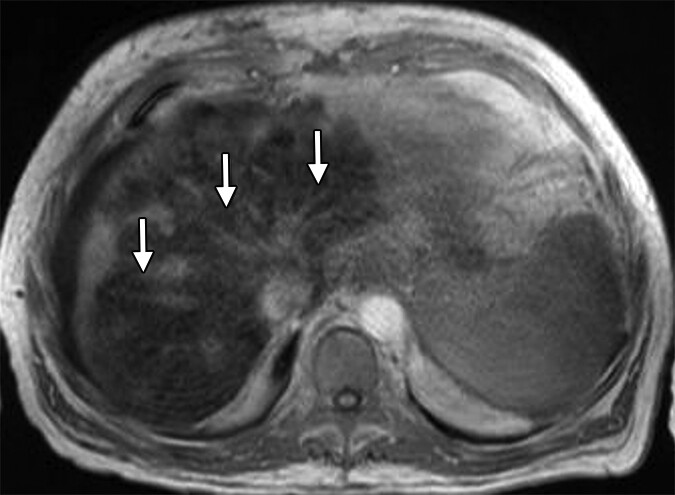

After 26 years specializing in liver health, I've reviewed thousands of scans like the one above. What's troubling isn't just what they show - it's who they're showing it in:

- Ultrasound showing early fatty changes with fibrotic development

- Follow-up ultrasound showed significant improvement in fatty changes